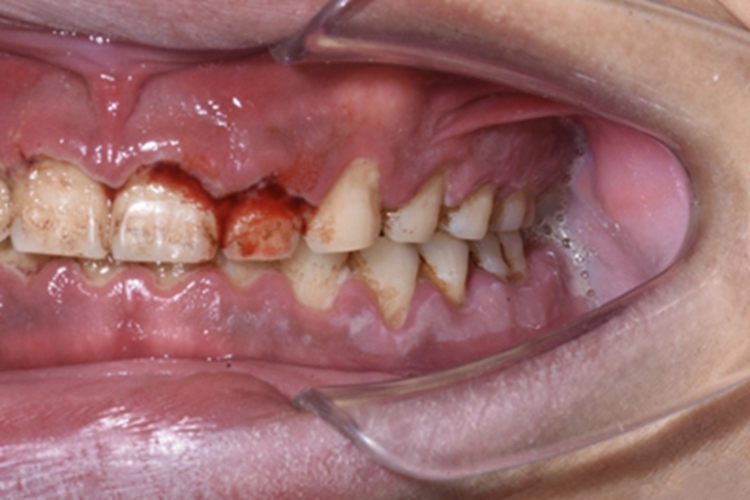

急性坏死性溃疡性龈炎起病急,病程短,常为数天至1-2周,以龈乳头和龈缘的坏死为其特征性损害,尤以下前牙多见,初起时龈乳头充血水肿,个别龈乳头顶端可发生坏死性溃疡,糜烂面上覆有灰白色坏死物,中央凹下如火山口状。龈缘如虫蚀状,坏死区出现灰褐色假膜,擦去后可见出血创面。龈乳头被破坏后与龈缘成一直线,如刀切状。病损一般不波及附着龈,患处牙龈极易出血,疼痛明显并有腐败性口臭。

重症患者可有低热、疲乏等全身症状,并可伴有下颌下淋巴结肿大和压痛。有的患者可能进展为坏死性龈口炎、坏死性溃疡性牙周炎等疾病,从而导致牙周袋形成、牙槽骨吸收和牙齿松动。